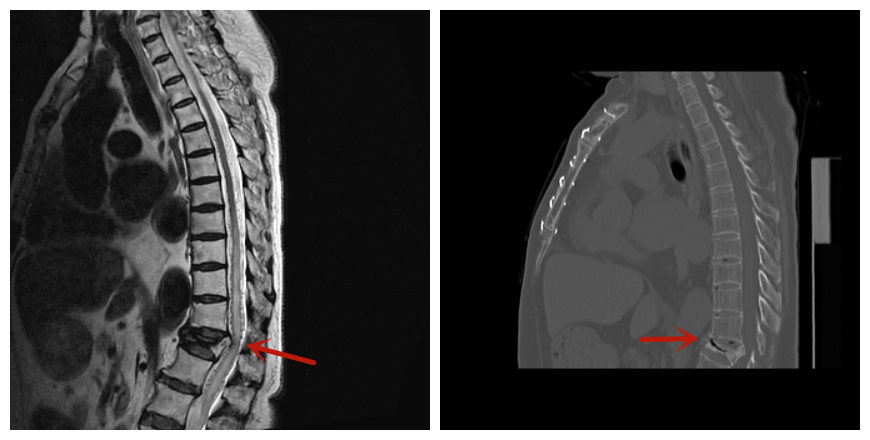

磁共振发现脊髓异常信号伴周围血管流空

后续检查提示,患者下肢肌力明显减弱,腱反射减退,双下肢腹股沟以下针刺觉减退,核磁检查提示胸腰段脊髓髓内高信号,伴周围异常血管流空影。结合病历资料,神经内科副主任冯新红立刻联系神经外科协助会诊,神经外科副主任医师吕宪利、主治医师张培海、医师梁士凯针对病情进行详细讨论,并为患者安排脊髓血管造影检查,最终确诊为硬脊膜动静脉瘘。